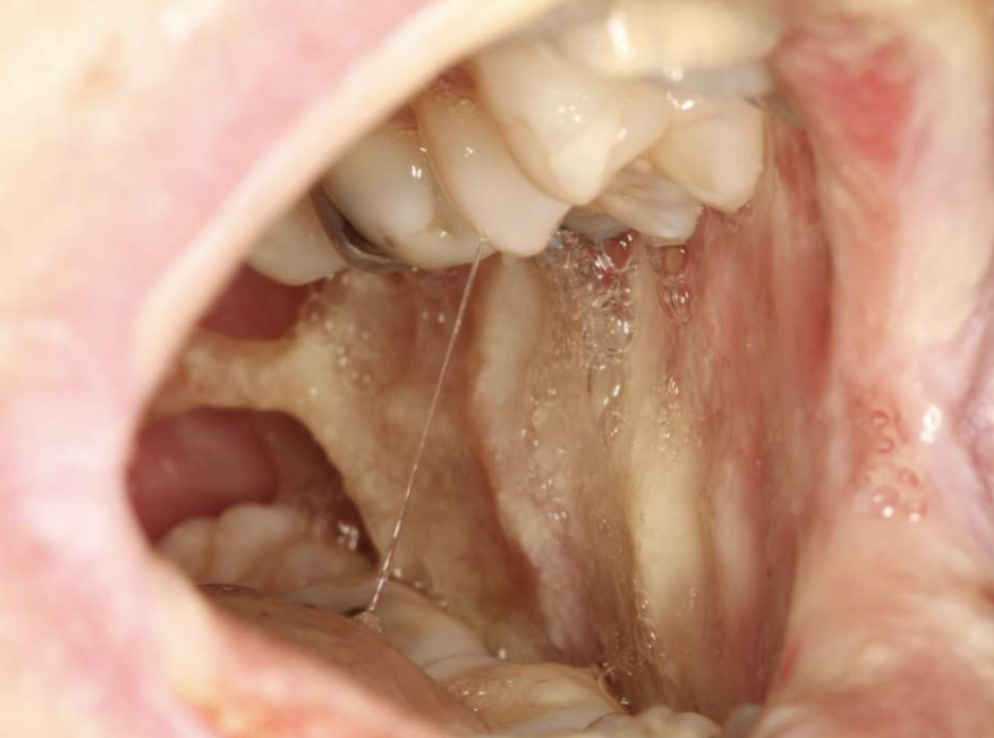

what is this

“Meth Mouth”

3 orofacial complications of meth abuse

xerostomia

bruxism

poor hygiene